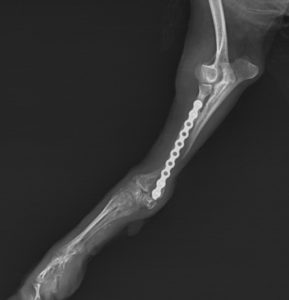

・内固定(プレート、ピン、スクリュー)

軽度の骨折では外固定のみで治癒することもありますが、多くの場合、安定した治癒を目指して手術が選択されます。

手術が必要になるケース

以下の場合は手術が強く推奨されます。

・骨のズレが大きい

・粉砕骨折

・関節を含む骨折

・成長板骨折

・小型犬の前足骨折

適切な手術により、痛みの早期軽減と機能回復が期待できます。

術後は安静管理が極めて重要で、運動制限を守れない場合、再骨折やインプラント破損につながることがあります。

合併症と注意点

骨折治療で注意すべき合併症には以下があります。

・感染

・癒合不全

・変形治癒

・関節可動域制限

術後の定期検診と画像評価が予後を大きく左右します。